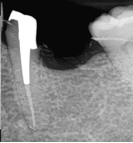

Conventional Endodontic Treatment with Post and Core Coronal Restoration

Conventional Endodontic Treatment/Retreatment with Prefabricated Bonded Post and Core